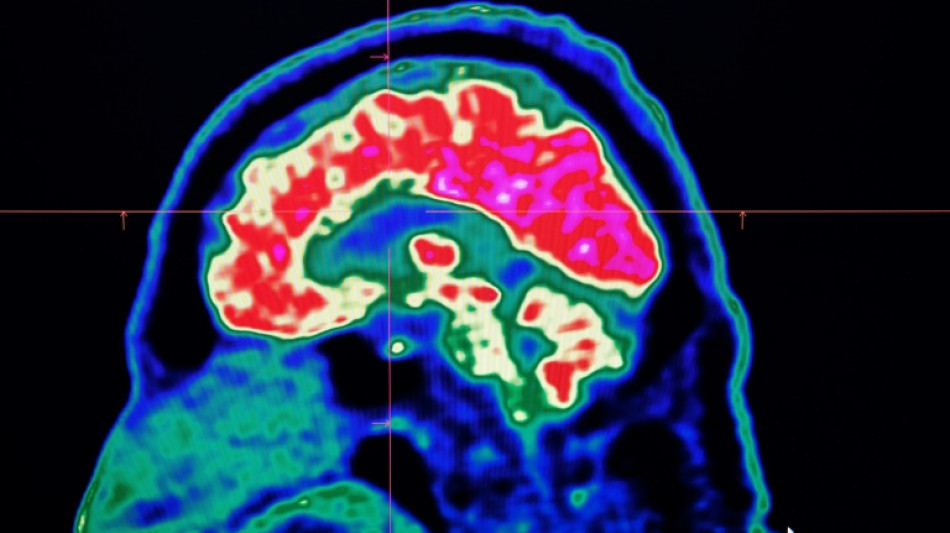

Surging nervous system disorders now top cause of illness: study / Photo: Fred TANNEAU - AFP/File